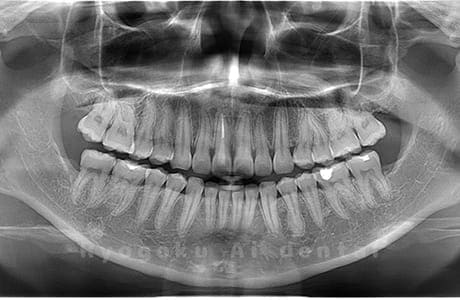

Case03

-

- 原因

- 上顎、下顎の親知らず

- 治療内容

- 上下4本の親知らずを抜歯したケースです。

<リスク・副作用>

手術後は痛み、腫れ、痺れなどの副作用が生じる場合があります。